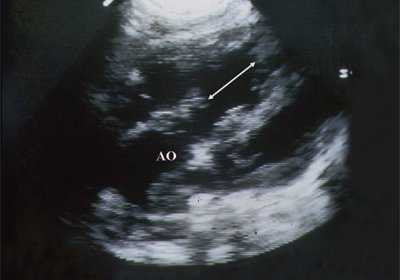

В равной степени это относится к дефекту межжелудочковой перегородки (рис. 6), простой форме транспозиции магистральных сосудов (рис. 7, 8), транспозиции магистральных сосудов с дефектом межжелудочковой перегородки (синдром Тауссиг - Бинга) (рис. 9), общему желудочку (рис. 10), общему артериальному стволу (рис. 10), двойному отхождению сосудов от одного из желудочков сердца (рис. 11).

Рис. 6. Дефект межжелудочковой перегородки. Длинная ось сердца. Стрелками показан дефект межжелудочковой перегородки.

Рис. 7. Транспозиция магистральных сосудов.

Рис. 8. Транспозиция магистральных сосудов, стрелками показаны ветви легочной артерии.

Рис. 9. Синдром Тауссиг - Бинга. Легочная артерия (отмечена стрелкой) расположена над дефектом межжелудочковой перегородки.

Рис. 10. Общий желудочек с отхождением TRUNCUS ARTERIOSUS. Стрелками показано разделение TRUNCUS ARTERIOSUS на аорту и ствол легочной артерии.

Рис. 11. Двойное отхождение магистральных сосудов от левого желудочка. Длинная ось сердца. Магистральные сосуды инвертированы и отходят от левого желудочка. Аорта расположена "верхом" над дефектом межжелудочковой перегородки (стрелка).

LV и RV - левый и правый желудочек, АР - легочная артерия, АО - аорта, VSD - дефект межжелудочковой перегородки.